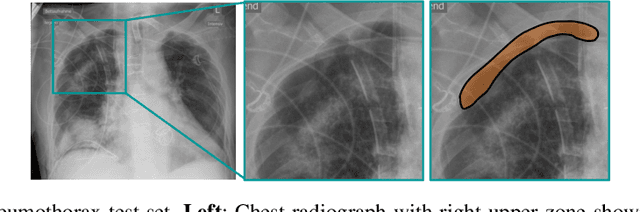

Abstract:Building accurate and robust artificial intelligence systems for medical image assessment requires not only the research and design of advanced deep learning models but also the creation of large and curated sets of annotated training examples. Constructing such datasets, however, is often very costly -- due to the complex nature of annotation tasks and the high level of expertise required for the interpretation of medical images (e.g., expert radiologists). To counter this limitation, we propose a method for self-supervised learning of rich image features based on contrastive learning and online feature clustering. For this purpose we leverage large training datasets of over 100,000,000 medical images of various modalities, including radiography, computed tomography (CT), magnetic resonance (MR) imaging and ultrasonography. We propose to use these features to guide model training in supervised and hybrid self-supervised/supervised regime on various downstream tasks. We highlight a number of advantages of this strategy on challenging image assessment problems in radiography, CT and MR: 1) Significant increase in accuracy compared to the state-of-the-art (e.g., AUC boost of 3-7% for detection of abnormalities from chest radiography scans and hemorrhage detection on brain CT); 2) Acceleration of model convergence during training by up to 85% compared to using no pretraining (e.g., 83% when training a model for detection of brain metastases in MR scans); 3) Increase in robustness to various image augmentations, such as intensity variations, rotations or scaling reflective of data variation seen in the field.